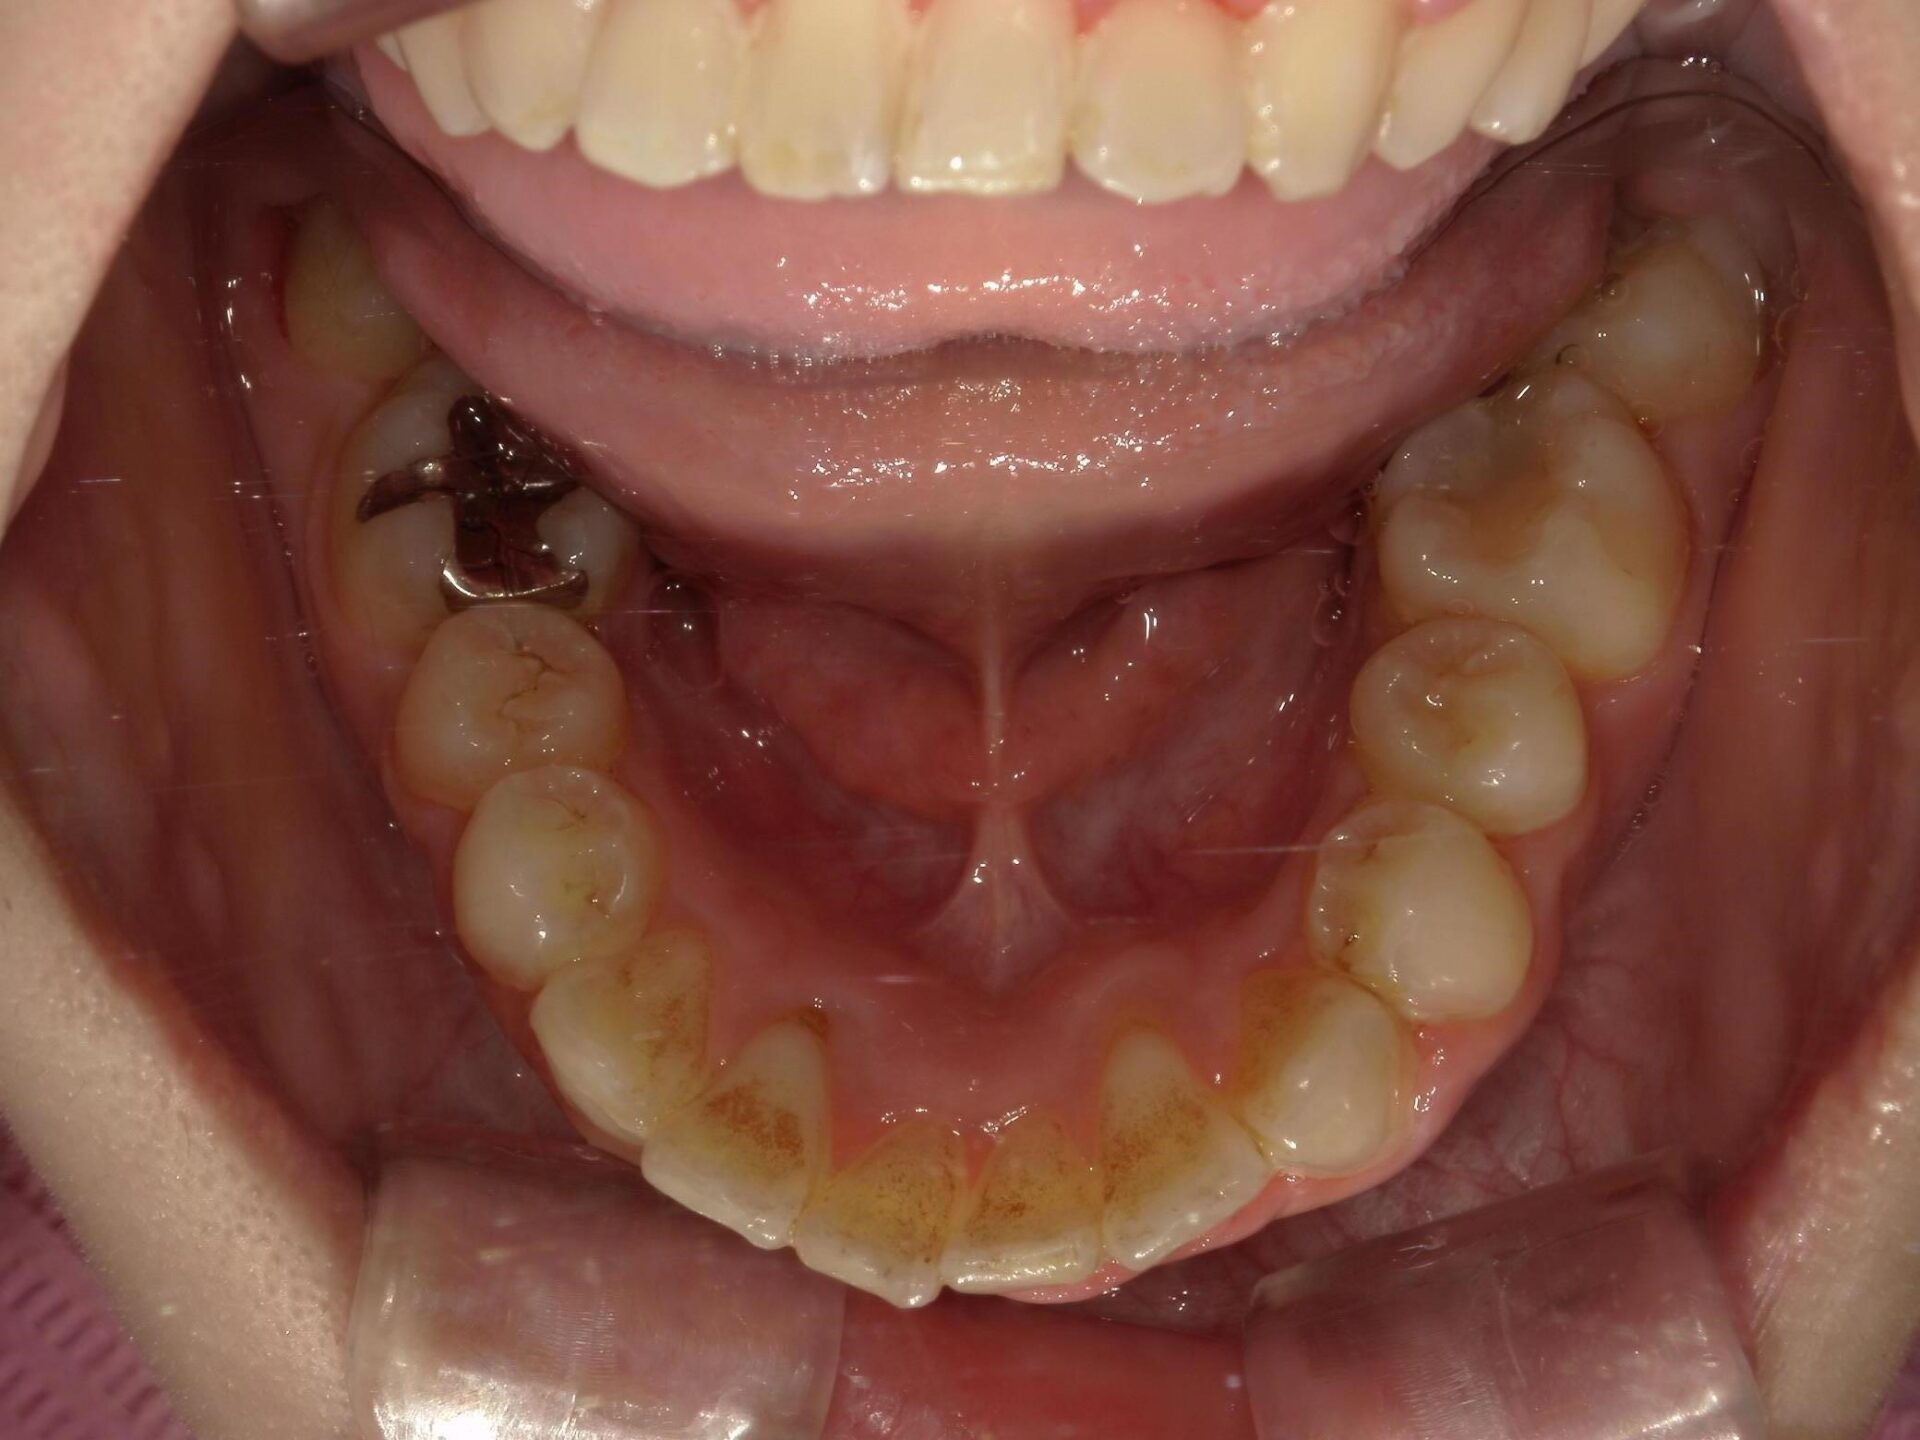

20代、男性、ワイヤー

| 施術内容 | 主訴:でこぼこで食べ物がよく挟まる。虫歯や歯肉炎に悩まされてきた。 詳細:ワイヤー矯正での歯並び改善 とても磨きやすくなったと満足されてます。 |

|---|---|

| 治療期間 | 16ヶ月(2/3現在 治療終了) |

| リスク・副作用 | ■リスク・副作用 ・治療の初期段階では、痛みや不快感が生じやすくなりますが、一週間前後で慣れます。 ・歯の動き方には個人差があるため、予想された治療期間より延長する場合があります。 |

| 費用 | ワイヤー矯正 60万円(税込660,000円) |